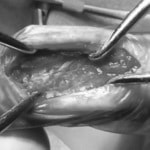

脊髄の減圧、脊柱管の再構築・安定化を目的に、片側椎弓切除術およびMatrixMANDIBLE Plateによる椎体固定を実施しました。

隣接椎体を架橋するようにプレートを設置しました。

術後レントゲン写真